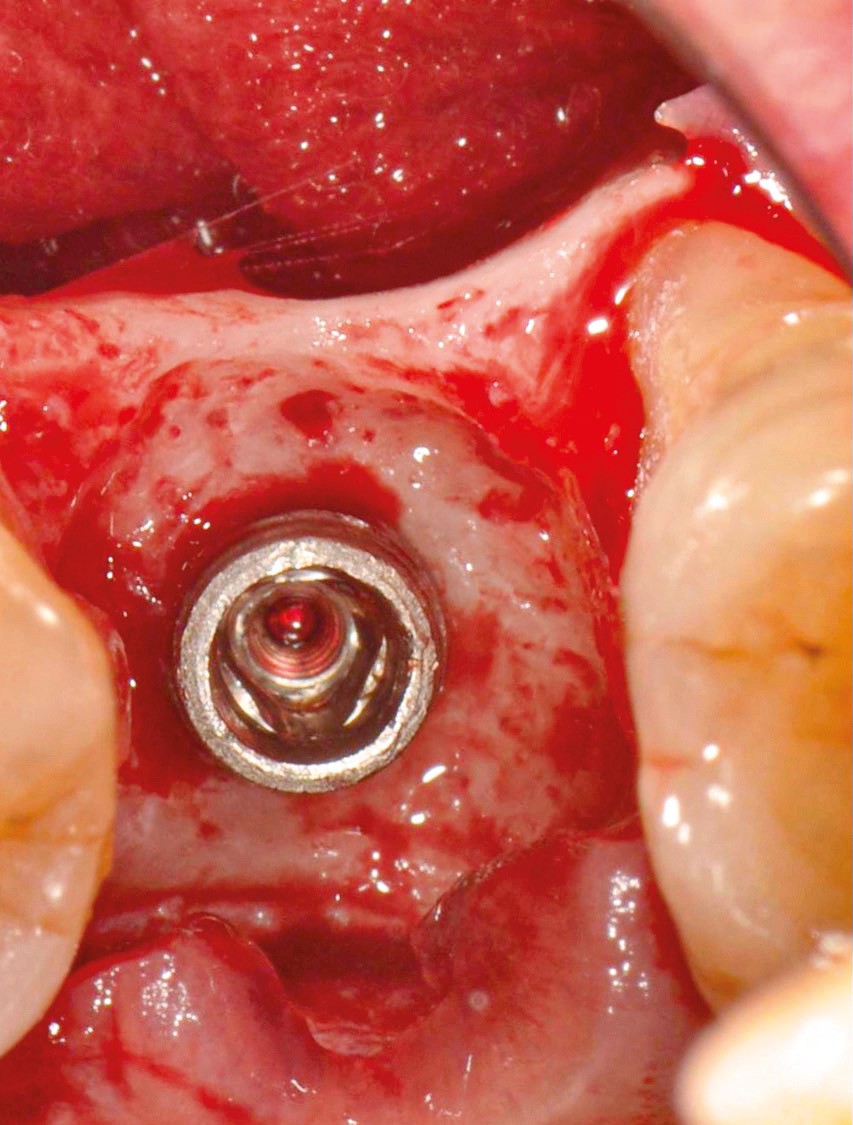

Chez cette patiente, le traitement de la péri-implantite a été réalisé à l’aide d’une technique de régénération osseuse guidée péri-implantaire, dont l’indication a été principalement motivée par la morphologie du défaut osseux. Au-delà de la maîtrise du geste chirurgical, le bon résultat obtenu à trois ans est intimement lié à sa coopération en termes de suivi et de contrôle de plaque.